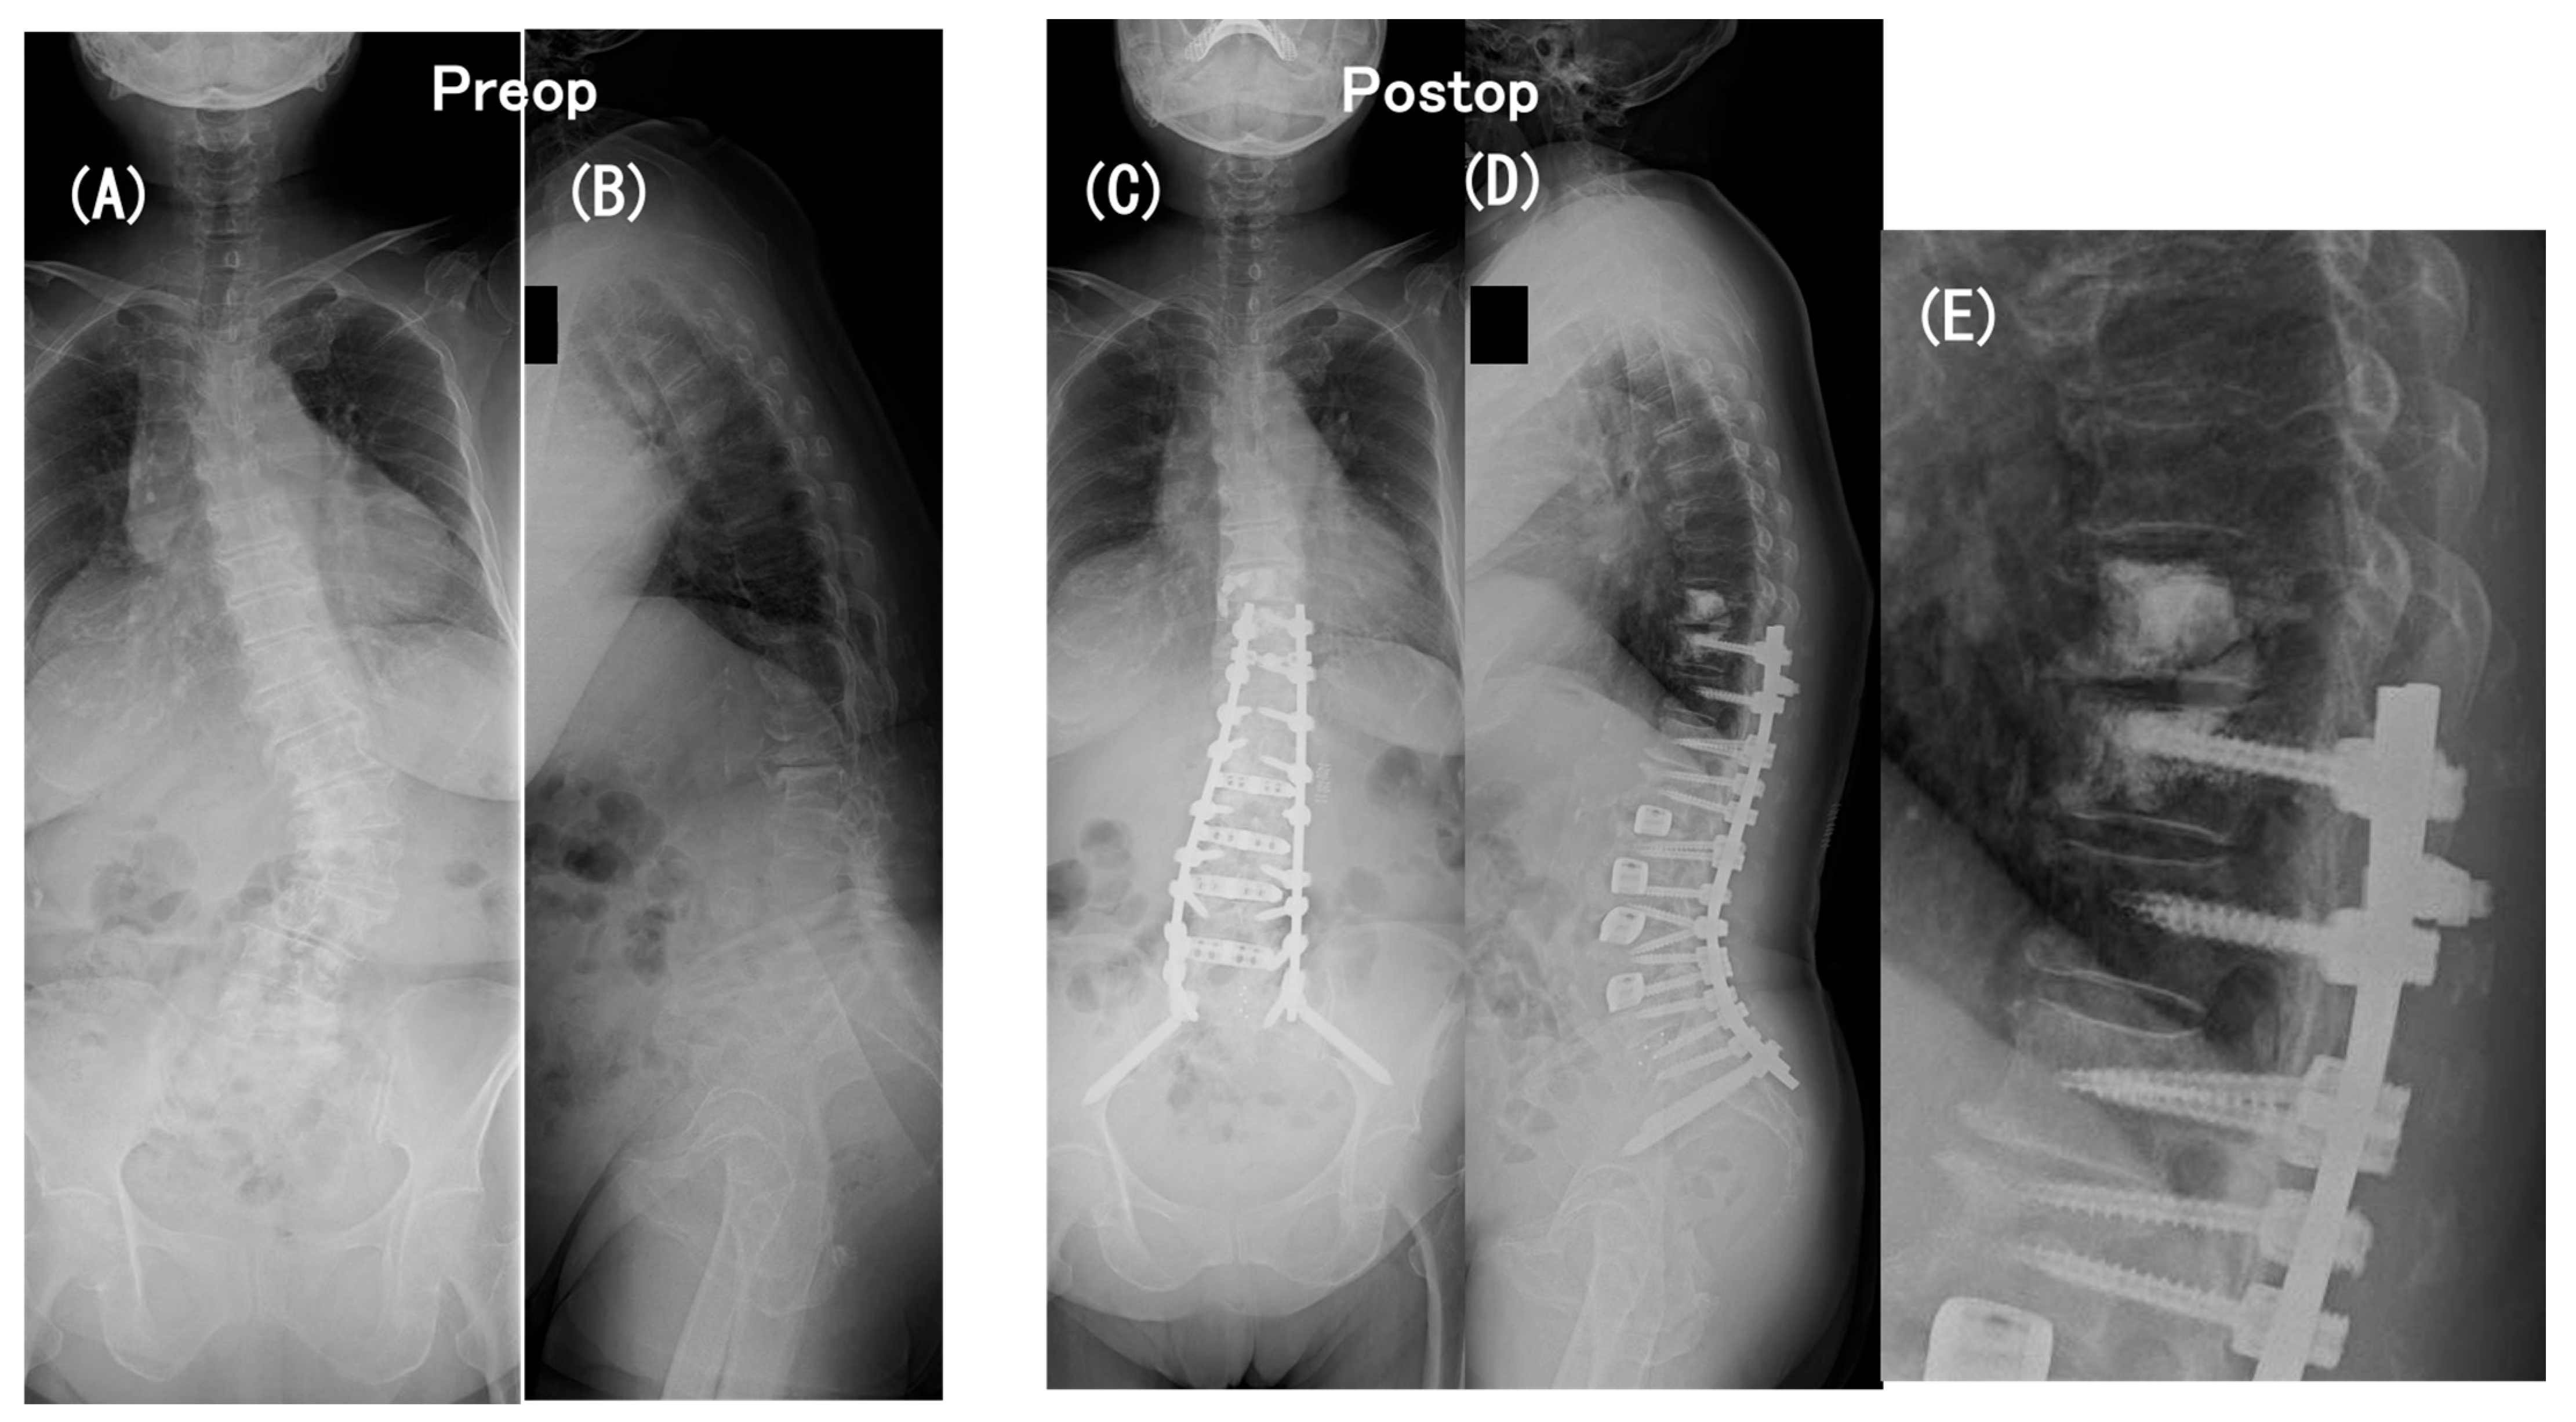

3.6. Case Presentation

- Case no. 6

- 2.

- Case no. 4